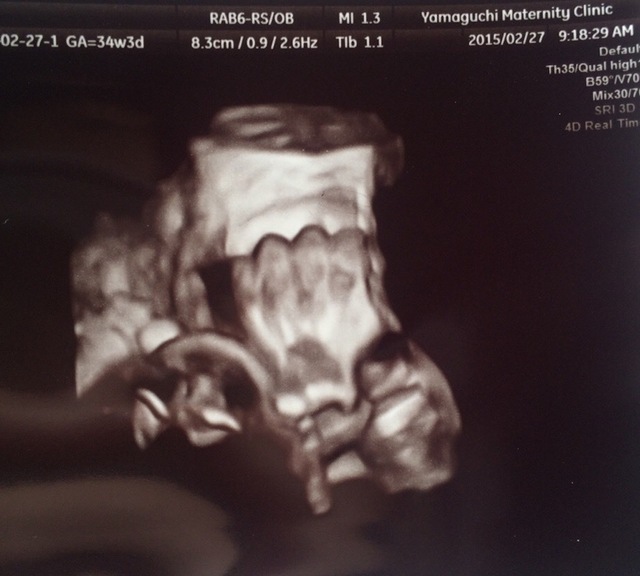

34週3日(34w3d・男の子)|hinaminaママ さん(23歳)

エコー写真撮影時のエピソード:

里帰り先の病院にて、初めての4dエコー。顔が見られるかとドキドキしながら診察を待っていました。

診察台に乗っていざ…先生が突然笑い出し何事かと思えば… 「ある意味すごくわかりやすいよー!今から喧嘩売ってるとか大物になりそう。」と笑いながらモニターを私の方に向けてくれました。

こんなはっきり映るものかと文明の力に感動した反面、確かに拳で喧嘩売ってるようにも見え、将来心配になりました。主人は息子のことよりも文明の力のことばかり話していました。

そんな子がいまではお兄ちゃん!喧嘩もするけど、今のところ拳を突き上げるような感じではなく優しく育っています。